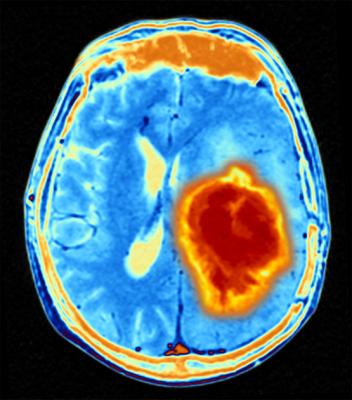

February 22, 2022 — Short bursts of radiation therapy dramatically enhanced the efficiency of targeting glioblastomas with natural nanoparticle-based immunotherapy, thus suppressing growth of the deadly tumor, inducing anti-tumor immunity and prolonging survival in animal models, a research team at Massachusetts General Hospital (MGH) has discovered. The combined strategy, described in ACS Nano, uses extracellular vesicles (EVs) to deliver the immunotherapeutic to the brain, bridging the blood-brain barrier and reversing immune suppression of both the tumor and the surrounding microenvironment.

Glioblastoma is the most common, deadliest and most treatment-resistant of cancers of the central nervous system, with a median survival of fewer than 15 months after standard-of-care surgery, chemotherapy and radiation therapy. While immune checkpoint blockade, a revolutionary new class of drugs that enables the body’s immune system to recognize and attack cancer cells, has produced responses in some cancers, glioblastoma has shown limited to no benefit. Scientists believe one reason may be the blood-brain barrier, composed of tightly packed cells in the brain’s capillaries that prevent medications from gaining entry to the brain. Another reason could be the profoundly immune suppressive environment characteristic of glioblastoma, and the narrow therapeutic window of dose escalation due to the potential for serious safety issues.